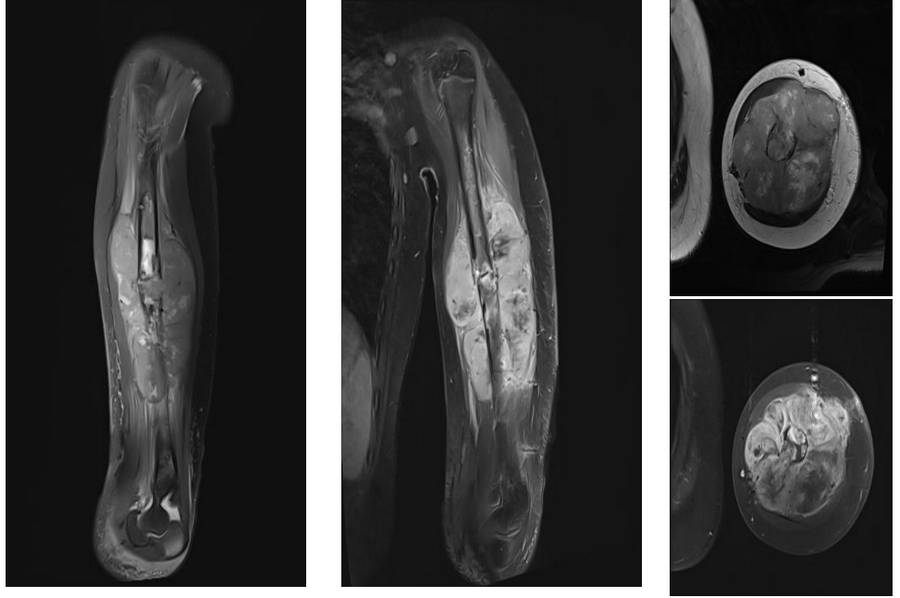

Ameliyat Öncesi: MR’da aynı lokalizasyonda kemikte patolojik kırığa neden olan heterojen, büyük boyutlu yumuşak doku komponentinin eşlik ettiği damar sinir paketini iten tümör dokusu görülmekte